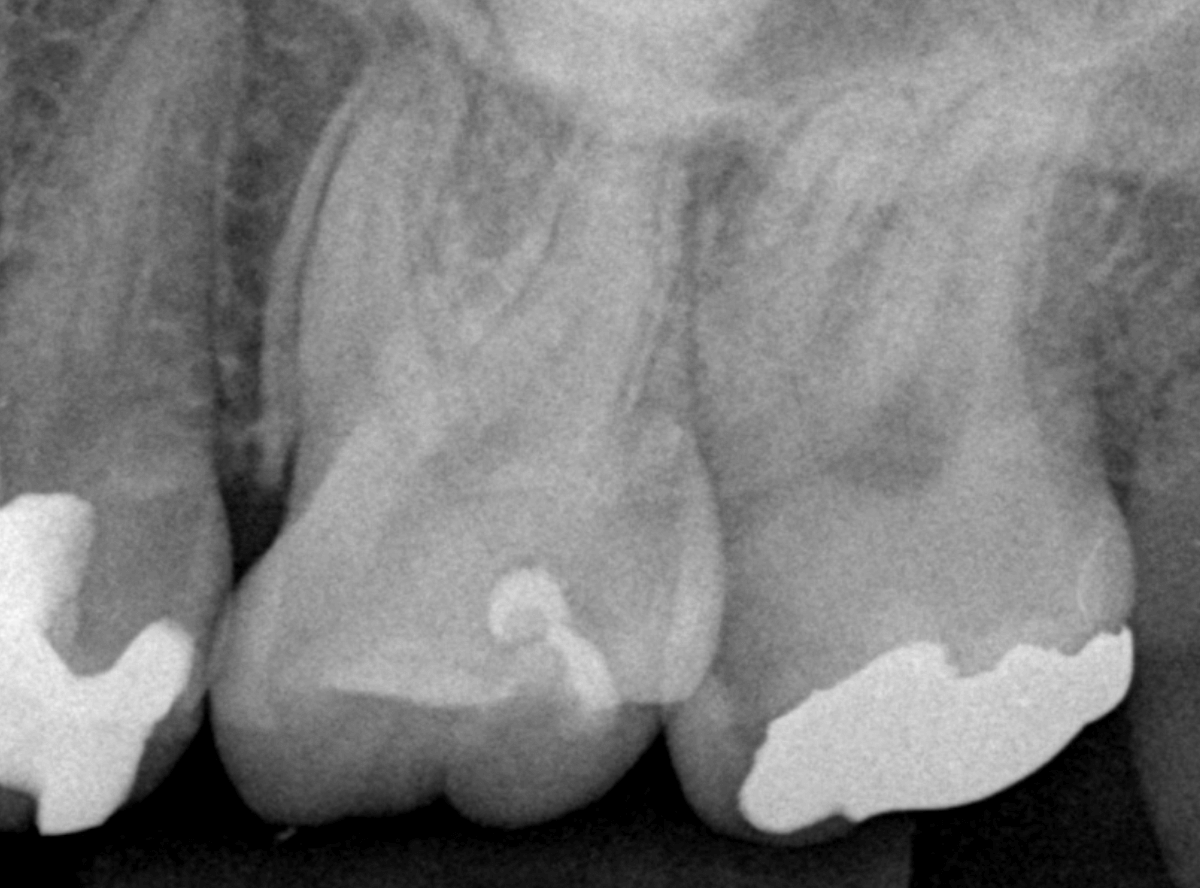

Case.14 インレーの下の歯肉まで広がった虫歯

「下の奥歯が噛むと痛む」という症状で来院された患者さんのケースです。

お口の中の状態を確認すると、奥歯の端に穴が開いているのが見えます。

レントゲン写真で確認します。

やはり、奥歯の端が大きな虫歯になっています。

青いラインが歯の神経、赤いラインが虫歯です。

レントゲン写真上では虫歯が神経まで達しているように見えます。

これは、神経を取らないとダメかもしれません。

中のお薬も慎重に外して虫歯を除去します。

虫歯が深く、歯肉の下まで浸食していましたので、歯肉を部分切除し、虫歯を全て除去したところで、奇跡的に神経スレスレの状態でとどまっていました。

何とも言えませんが、神経を残せる可能性が出てきました。

虫歯が神経まで達していなくても、治療前から自発痛(何もしなくても痛い)があれば、神経をとらなければいけません。

今回は、そこまでの症状がありませんでしたので、患者さんと相談の上、神経を取らずに残す方法で様子を見る事になりました。

痛みが出ませんように。。。